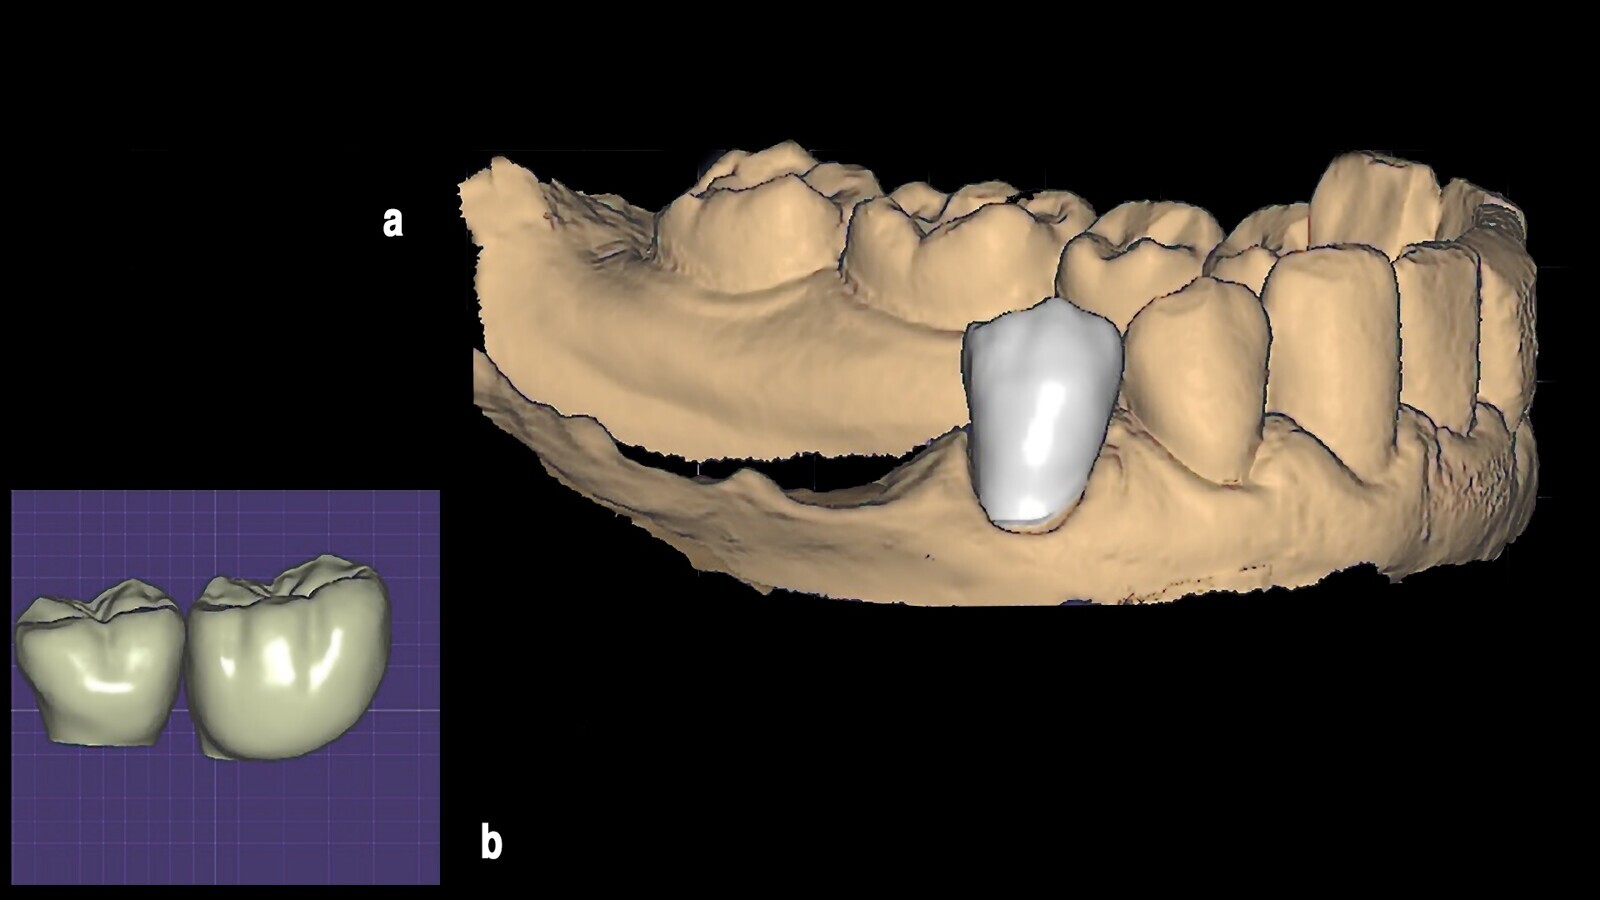

Figura 5. Mediante la "lectura" del antiguo pilar, fue posible identificar el paso de rosca y la plataforma del implante (5a) para obtener, además del kit mencionado, dos pilares Equator de OT personalizados (5b).

Figura 15. El escaneado permitió la confección del provisional mediante técnica digital.

Figura 16. Los provisionales fueron diseñados y fresados con la técnica CAD-CAM.